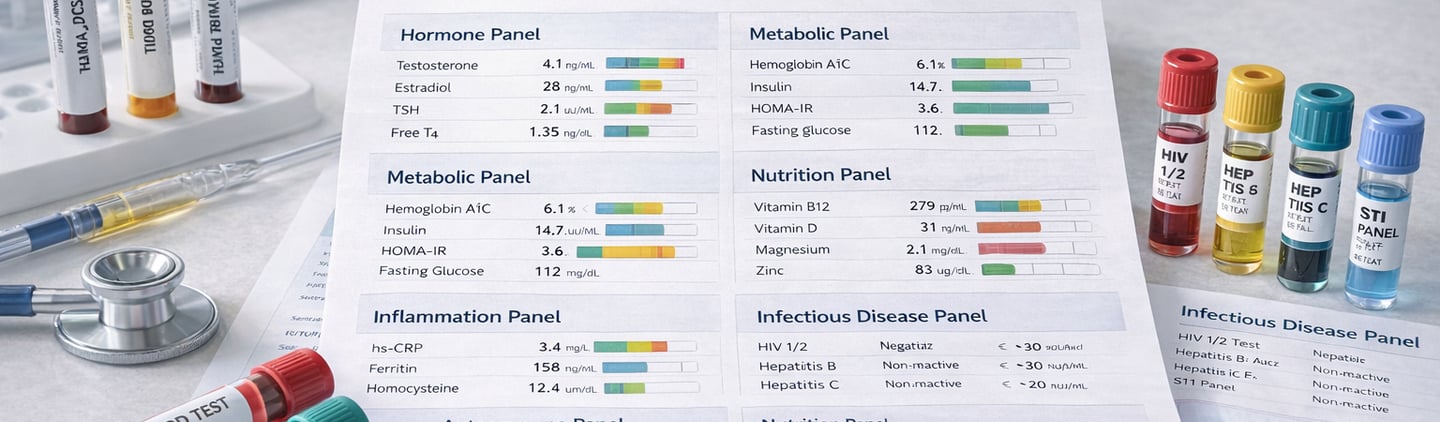

🧪 Laboratory & Biomarker Analysis

From numbers to meaning

Comprehensive blood work (hematology, biochemistry, lipid, endocrine)

Hormonal systems (testosterone, estrogen, thyroid, adrenal axis)

Inflammatory and metabolic markers (CRP, A1C, insulin, HOMA-IR)

Nutritional status (vitamins, micronutrients, trace elements)

Liver, kidney, and electrolyte panels

Autoimmune screening (ANA, ENA, RF, anti-CCP)

Infectious disease testing (HIV, hepatitis, STIs)

Advanced cardiovascular biomarkers (Lp(a), ApoB, hs-CRP)